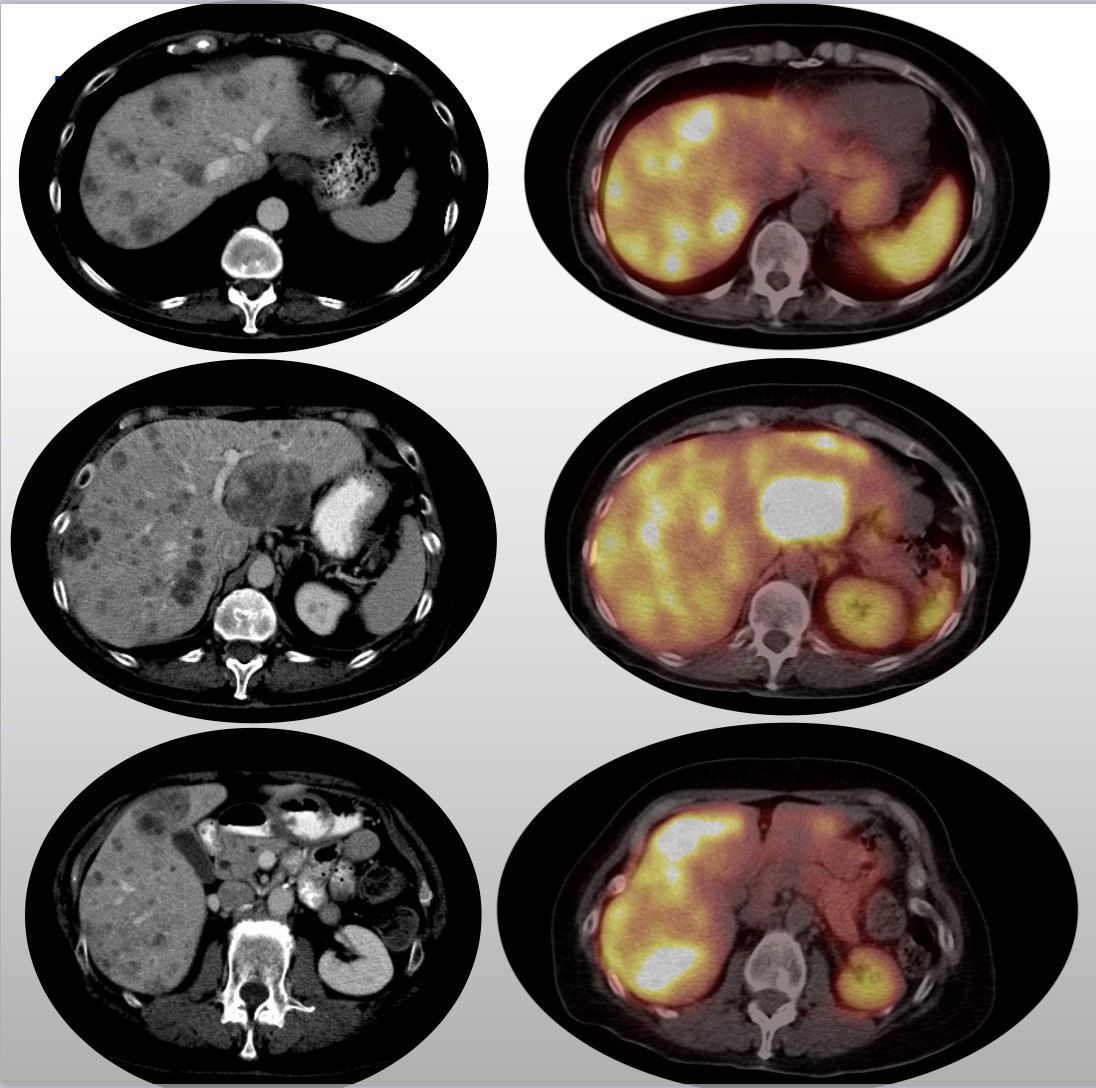

A male patient with hepatic neuroendocrine tumor metastases, with the

Metabolically active liver metastases of a rectal neuroendocrine tumor Neuroendocrine Cancer Metastasis Liver What are the symptoms of neuroendocrine liver cancer? liver surgery with the intention to cure is the treatment of choice for. here we will delve into the diverse approaches for managing neuroendocrine metastatic liver cancer,. Once considered exceptionally rare, neuroendocrine tumors (net) are increasingly common and. the most common sites of metastasis for neuroendocrine tumours include the. Neuroendocrine Cancer Metastasis Liver.